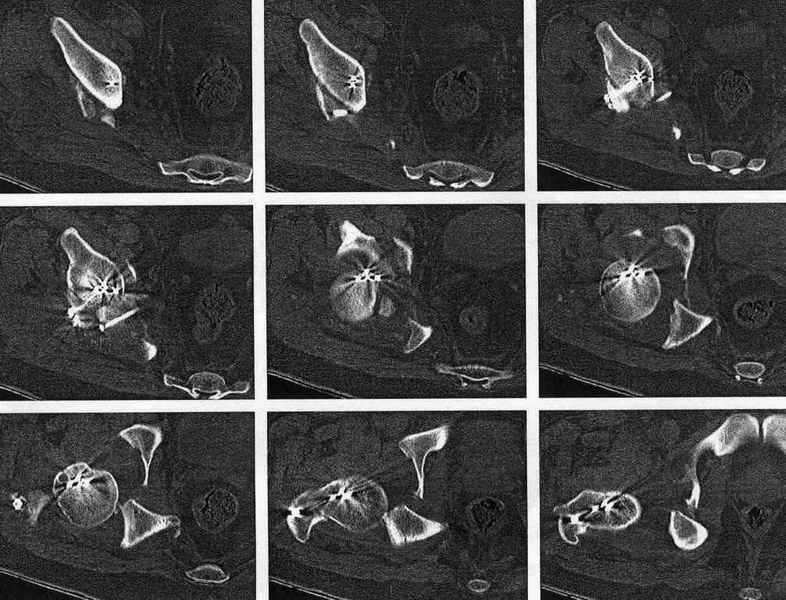

Мужчина 32 года, автотравма 6 недель назад. При поступлении был установлен диагноз "Ацетабулярный перелом". Вывих бедра не был установлен.

После установления вывиха бедра через 3 недели после травмы больному выполнена попытка открытой репозиции, остеосинтез вертлюжной впадины, Бедро фииксировано трансартикулярно спицами. После операции неврит седалищного нерва. В течение ещё 3-х недель после операции установлено что отломки не репонированы, вывих бедра не устранён (см. КТ и рентгенограмму), неврологической динамики нет. Возние вопрос о повторном оперативном вмешательстве по поводу чего разгорелись жаркие споры и сформировалось следующие мнения:1. Тотальное эндопротезирование с цементной фиксацией чашки протезом "ЭСИ" (другого протеза нет)2. Повторная открытая репозиция бедра с замещением дефектов вертлюжной впадины аутокостью с целью подготовки для последующего эндопротезирование. Предполагается фиксация тазобедренного сустава в послеоперационном периоде гипсовой повязкой или аппаратом внешней фиксации.Прошу высказать ваше мнение о тактике дальнейшего лечения пациента, о предложенных вариантах. Отдельный вопрос о возможности первичного тотального эндопротезирования при ацетабулярных переломах. (Лечащий врач настаивал перед первой операцией на выполнении тотального эндопротезирование с цементной фиксацией чашки через 3 недели после травмы)

Представленный перелом вертлужной впадины характеризуется нарушением непрерывности тазового кольца, обусловленный переломом передней и задней колонн, вполне возможно и с повреждением weightbearing surface- по прямой рентгенограмме сложно однозначно судить, а представленные томограммы не захватывают несущую поверхность впадины. Экспресс протезирование однозначно не показано - фиксировать ацетабулярный компонент не к чему, а цемент *уйдет* в зоны перелома. Достаточно обширное вмешательство должно быть направлено на восстановление целостности тазового кольца(передний забрюшинный доступ) и фиксация реконструктивной пластиной, после чего пациент поворачивается на бок или на живот и на тракционном столе из заднего доступа фиксируется задняя колонна реконструктивной пластиной. Для репозиции фрагментов нужно иметь тазовые зажимы (pelvic reduction clamps), без которых достичь желаемого результата технически сложно. Оптимальное время хирургии через неделю, 10 дней , когда общее состояние больного стабилизируется и закончено активное кровотечение из отломков. Хорошо бы иметь cell saver для таких случаев, а если нет - интраоперационная гемотрансфузия донорской крови.

Было бы существенным посмотреть обзорную R-грамму до операции. По данным послеоперационных снимков и КТ имеется низкий двухколонный перелом или

высокий Т-образный перелом с отрывом свода. Для уточнения необходиы косые проекции (Judet). Весь ли седалищный нерв молчит или только м/б порция?

Высылаю прямой обзорный и косой подвзошный снимки, косой запирательный неудовлетворительного качества.